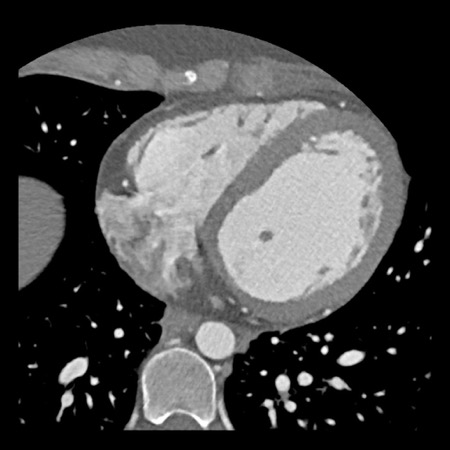

case 2 – CAD-RADS 5/P2/S

First, scroll through the CTA images.

How would you describe the findings on the coronary CTA?

The findings are:

- Stent in the mid

LAD with low-attenuation within the stent suggestive of minimal in-stent

restenosis (<25%). Non-calcified plaque distal to the stent

causing mild stenosis (25-49%). Notice bridging on a short segment in

the distal LAD. - Non-calcified

plaque in the LCX causing mild stenosis (25-49%). - Occlusion of the

proximal OM1 branch with distal filling. - Calcified and

non-calcified plaques in the proximal RCA causing mild (25-49%) stenosis. - Total plaque burden

is moderate based on SIS (four segments including proximal RCA, mid LAD, prox

LCX and OM1).

Due to the occlusion of OM1 branch and presence of the stent, this case

reads as CAD-RADS 5/P2/S, which means that this patient needs further

diagnostic workup.